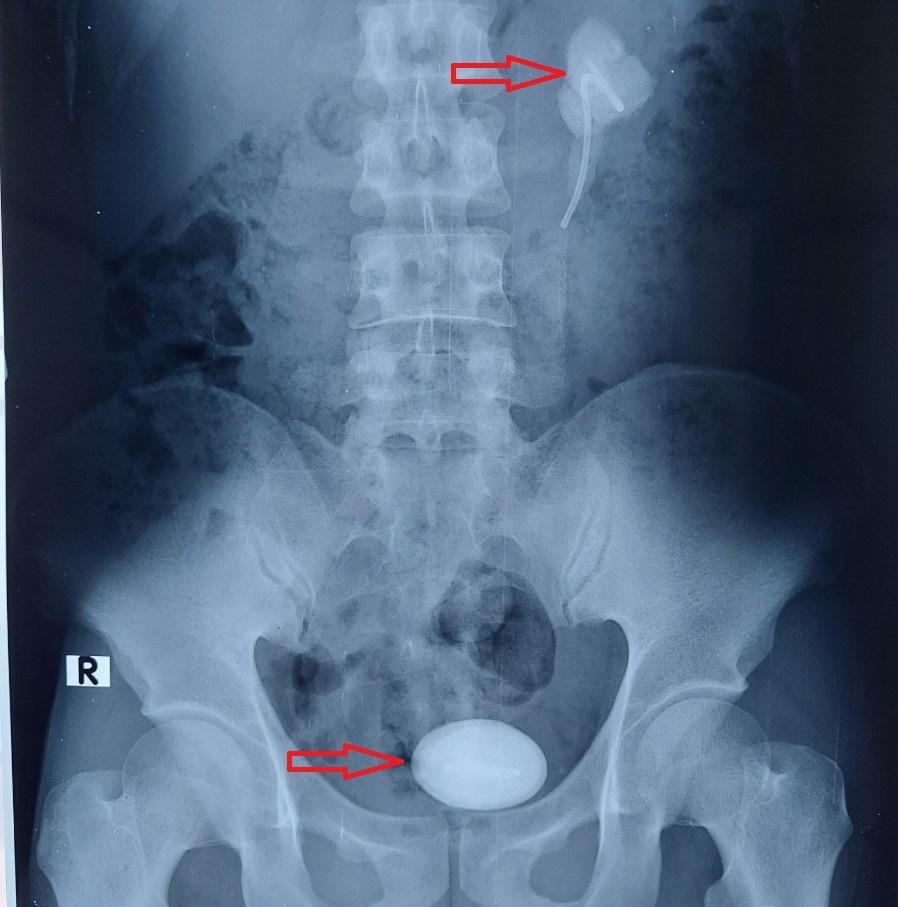

Hình ảnh sỏi thận trái và bàng quang còn 1 ống JJ (trái) Ảnh: BVCC |

Các bác sĩ đã chỉ định siêu âm và chụp cắt lớp vi tính hệ niệu ghi nhận, thận trái ứ nước độ II, sỏi vùng bể thận – niệu quản bên trái, kích thước 30x58 mm, sỏi bàng quang kích thước 90x58 mm, có 1 đoạn ống thông JJ trong cả 2 viên sỏi. Sau hội chẩn quyết định phẫu thuật nội soi sau phúc mạc lấy sỏi thận trái sau đó mổ hở lấy sỏi bàng quang.